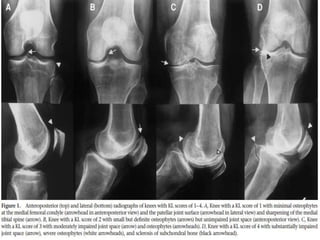

 RADIOLOGICAL FEATURES:

◦ CARTILAGE LOSS

◦ SUBCHONDRAL SCLEROSIS

◦ CYSTS

◦ OSTEOPHYTES